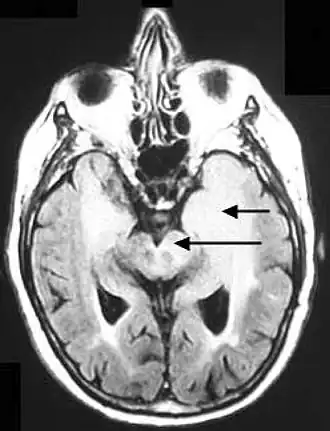

![]() Аксиальная FLUID МРТ, демонстрирующая инфильтративный рост опухоли с вовлечением обеих лобных долей (короткая стрелка) и чёрного вещества (длинная стрелка). | |

Глиоматоз головного мозга - редкая разновидность диффузной глиальной опухоли, широко инфильтрирующая головной мозг, вовлекающая две и более доли (нередко билатерально) и часто распространяющаяся инфратенториально. Сам термин введен в обиход в 1938[1] году и с тех пор в литературе описано около 200 случаев. Несмотря на активные исследования данного заболевания и научные поиски, до сих остаётся неясным является ли глиоматоз формой диффузно-инфильтративной глиомы или же представляет собой самостоятельный патологический синдром.